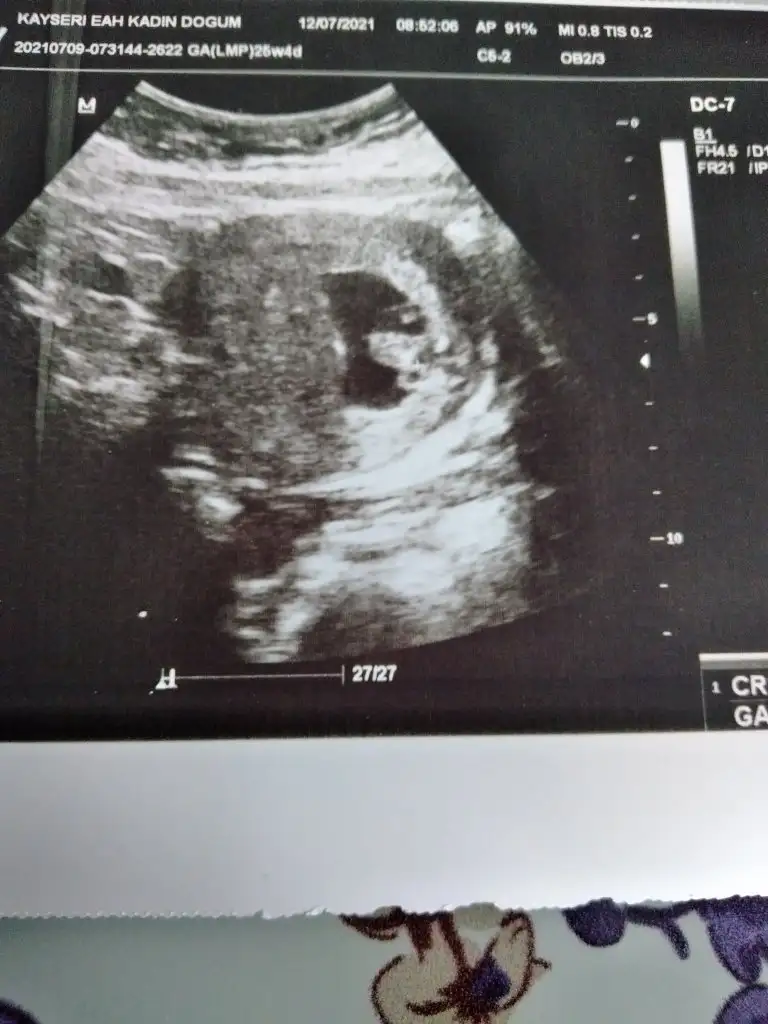

Evet karından gördük ancak kalp atışı çok zor duyuluyor, duyamazsanız panik yapmayın :)Merhaba ters rahim de 7 haftada karından goruluyir mu acaba ben de ayniyim

KızBana da bakabilirmisin canım 7+4 haftalik karından çekildi ultrason